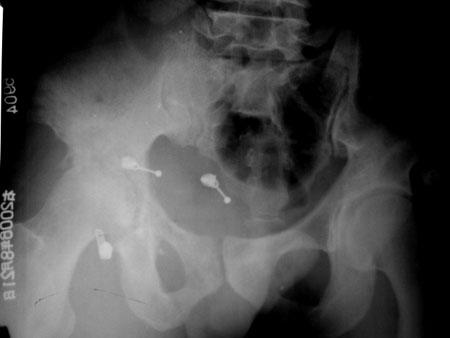

患者,男,48岁,右大腿及右膝关节功能障碍就诊,病人入院时,由家属背入,消瘦,右膝及右髋关节活动障碍,不能伸直,以下是右股骨和双髋关节平片.

右侧股骨头及髋臼相邻关节面骨质见明显破坏,边界不清,关节面皮质缘大部消失,无明显骨质增生,间隙变窄,周围软组织明显肿胀.(图像不理想)

考虑:右髋关节结核可能性大.

考虑右髋关节结核.理由:

1.右髋关节邻近骨质疏讼;

2.关节间隙狭窄;

3.髋臼及股骨头的骨质破坏.

建议ct并增强.

首先考虑髋关节结核.因为髋骨呈虫噬样破坏,并且右大腿软组织内见斑点状钙化.

右侧股骨头及髋臼相邻关节面骨质见明显破坏,边界不清,关节面皮质缘大部消失,无明显骨质增生,间隙变窄,周围软组织明显肿胀.(图像不理想)结合病人家属有结核史

考虑:右髋关节结核